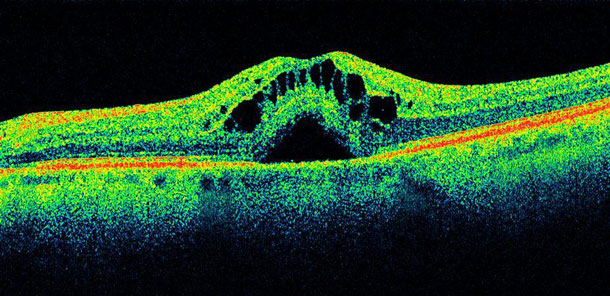

Our diabetes package includes a comprehensive eye examdilated pupil examinationvisual field test and extensive OCT scans of the optic nerve, macula and peripheral retina.